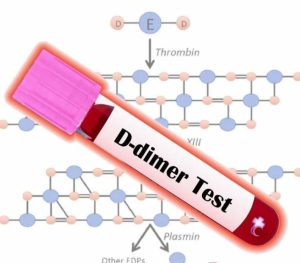

آزمایش D‑dimer معمولاً برای رد احتمال لخته خون بهکار میرود؛ اما در برخی بیماران، بالا بودن مزمن آن میتواند نشانهای از فعالیت مداوم سیستم انعقادی و ریسک پنهان سکته مغزی یا قلبی باشد. یکی از شرایطی که چنین تغییر ظریفی را در نتایج آزمایش آشکار میکند، سندروم آنتیفسفولیپید پنهان (Latent APS) یا APS نهفته است؛ اختلالی که ممکن است سالها بدون علامت بماند، اما در نهایت به یک واقعه ترومبوتیک جدی منجر شود.

D‑dimer چیست و چرا بالا میماند؟

D‑dimer محصول نهایی تجزیه فیبرین است، یعنی زمانی در خون افزایش مییابد که لختهای تشکیل شده و سپس توسط سیستم فیبرینولیتیک تخریب شود.

افزایش پایدار D‑dimer برخلاف افزایش گذرای آن، به معنی وجود فعالیت مداوم میکروترومبوز و تخریب فیبرین در عروق کوچک است؛ حالتی که در APS پنهان، بدون بروز علائم بالینی آشکار، میتواند سالها وجود داشته باشد.

در چنین شرایطی، سطح D‑dimer به شکل مزمن بالا میماند، حتی در غیاب نشانههای ظاهری ترومبوز. این افزایش مداوم، در واقع سیگنال هشدار بدن از وجود فعالیت لختهسازی زیرسطحی است.

در بیماران با آنتیبادیهای فسفولیپیدی مثبت ولی بدون سابقه لخته، بررسی دورهای D‑dimer میتواند تستی حیاتی در پایش خطر سکته و آنفارکتوس خاموش باشد.

پایش منظم با D‑dimer، سطح آنتیبادیها و شاخصهای التهابی، نقشی کلیدی در ارزیابی اثربخشی درمان دارد.

D‑dimer مزمن بالا در APS نهفته تنها یک عدد آزمایشگاهی نیست، بلکه پیام بدن از وجود التهاب عروقی و لختهسازی مداوم است. شناسایی زودهنگام و پایش منظم آن میتواند از بروز سکته، آنفارکتوس و ترومبوزهای خطرناک پیشگیری کند. در بیماران دارای ریسک خودایمنی، این شاخص باید با دقت و پیگیری دورهای تحلیل شود.